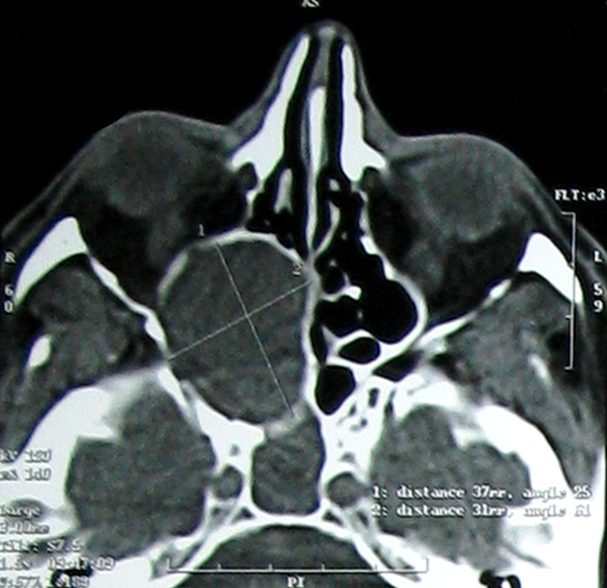

Une mucocèle est une tumeur bénigne pseudo-kystique, se développant dans les sinus de la face. Elle siège le plus souvent au niveau du complexe éthmoïdo-frontal. La localisation sphénoïdale est rare (1 à 2 % des mucocèles sinusiennes). La symptomatologie non spécifique des mucocèles sphénoïdales doit impérativement conduire à la réalisation d'une endoscopie nasale et la demande d'une imagerie afin de proposer une prise en charge thérapeutique précoce évitant ainsi les séquelles ophtalmologiques irréversibles. Homme âgé de 45 ans sans antécédents particuliers a consulté pour exophtalmie, baisse de l'acuité visuelle et épistaxis. L'examen physique a objectivé une exophtalmie droite et une baisse de l'acuité visuelle. L'examen biologique a retrouvé un discret syndrome inflammatoire. L'endoscopie nasale a révélé un bombement du récessus ethmoïdo-sphénoïdal. La TDM du massif facial en coupe axiale a montré un processus expansif sphénoïdal et ethmoïdal postérieur droit qui comprime le nerf optique et souffle les parois osseuses. L'IRM du massif facial en coupes axiales et en pondération T1 injecté et T2 a objectivé le même processus en hypersignal après injection de gadolinium et en hypersignal T2. Plusieurs diagnostics ont été évoqués en particulier un lymphome ou une néoplasie solide. Le traitement s'est basé sur une marsupialisation et une sphénoïdotomie. Les suites opératoires étaient simples. L'examen anatomo-pathologique a conclut à une mucocèle. L'évolution était marquée par une régression incomplète des troubles visuels sans notion de récidive avec un recul de 36 mois.